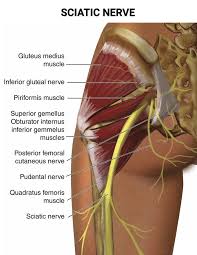

Download Sciatic nerve pain pictures